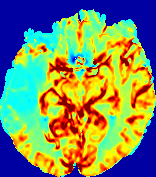

4.3.2 Diffusion Imaging via Advection-Diffusion

Slice #1Slice #2Slice #3Slice #4Slice #5Slice #6Dgtsuperscript𝐷gtD^{\text{gt}}Refer to captionRefer to captionRefer to captionRefer to captionRefer to captionRefer to captionDestsuperscript𝐷estD^{\text{est}}Refer to captionRefer to captionRefer to captionRefer to captionRefer to captionRefer to captionRefer to caption0.300.300.300.240.240.240.180.180.180.120.120.120.060.060.060.000.000.00(mm2/s)𝑚superscript𝑚2𝑠(mm^{2}/s)𝐕est𝟐subscriptnormsuperscript𝐕est2\|\bf{V}^{\text{est}}\|_{2}Refer to captionRefer to captionRefer to captionRefer to captionRefer to captionRefer to captionRefer to caption0.00300.00300.00300.00240.00240.00240.00180.00180.00180.00120.00120.00120.00060.00060.00060.00000.00000.0000(mm/s)𝑚𝑚𝑠(mm/s)

Figure 15: PIANO identifiability testing: diffusion imaging via advection-diffusion. Top row shows Dgtsuperscript𝐷gtD^{\text{gt}} used for simulating ground truth pure diffusion. Rows below show the estimated Destsuperscript𝐷estD^{\text{est}} and 𝐕est2subscriptnormsuperscript𝐕est2\|{\bf{V}}^{\text{est}}\|_{2} on corresponding slices. Note that the plotted value scale for 𝐕est2subscriptnormsuperscript𝐕est2\|{\bf{V}}^{\text{est}}\|_{2} is 0.01 of that for Dgtsuperscript𝐷gtD^{\text{gt}} and Destsuperscript𝐷estD^{\text{est}}.

Similarly, we test the behavior of PIANO when estimating both advection and diffusion from a pure diffusion-driven process. The goal is to determine if PIANO is able to recognize that there is only diffusion governing the given concentration time-series. We use the same ‘Diffusion Imaging’ data simulation of Sec. 4.2.1 as the concentration dataset, PIANO estimates both velocity 𝐕estsuperscript𝐕est{\bf{V}}^{\text{est}} and diffusivity Destsuperscript𝐷estD^{\text{est}}. Estimation results in Fig. 15 confirm PIANO’s identifiability again: the estimated 𝐕est2subscriptnormsuperscript𝐕est2\|{\bf{V}}^{\text{est}}\|_{2} is almost invisible compared to Destsuperscript𝐷estD^{\text{est}}, even plotted with a 1%percent11\% value range compared to that for Destsuperscript𝐷estD^{\text{est}}. On the other hand, Destsuperscript𝐷estD^{\text{est}} achieves comparable estimation performance as ‘Diffusion Imaging via Diffusion’ in which PIANO predicts Destsuperscript𝐷estD^{\text{est}} alone (shown in Fig. 13).